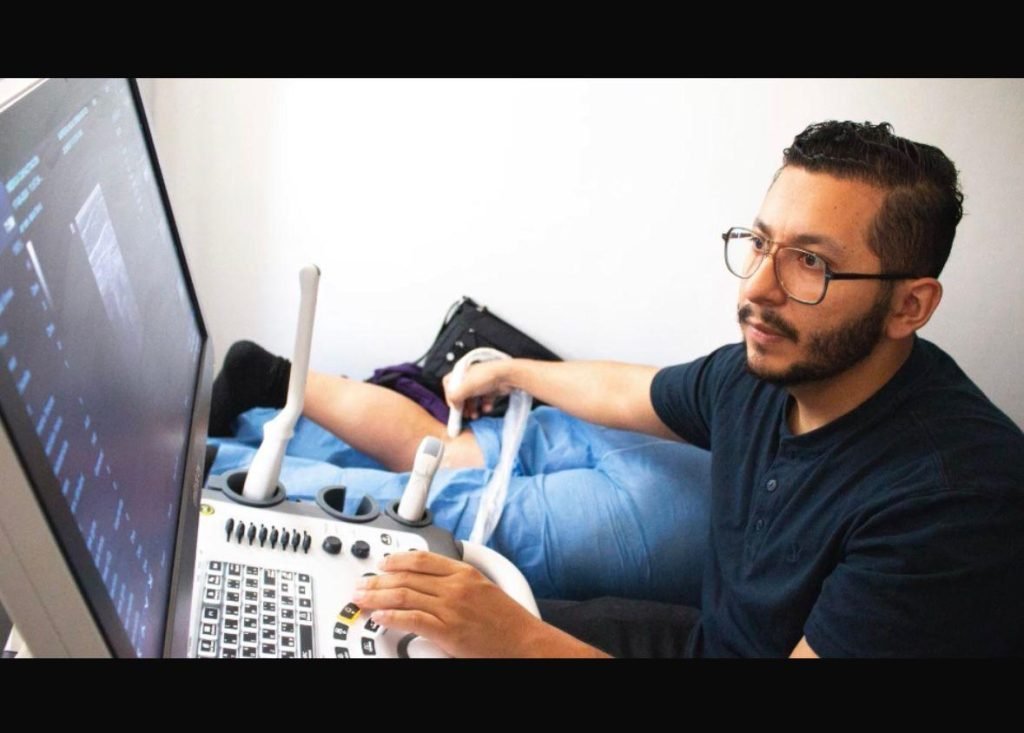

Procedimientos en traumatología y ortopedia | Dr. Luis F. Gómez

Como cirujano ortopedista, aplico infiltraciones en la rodilla para aliviar el dolor y la inflamación causados por artrosis u otras lesiones articulares. Utilizo medicamentos como corticosteroides o ácido hialurónico, dependiendo del caso. Este procedimiento es rápido, seguro y no quirúrgico, ideal para mejorar la función de la rodilla y evitar o retrasar una cirugía en muchos pacientes.